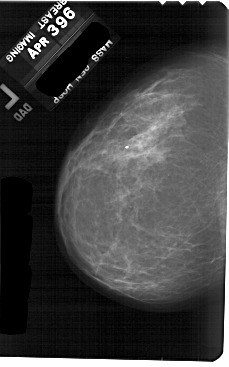

A_1886_1.LEFT_MLO

LEFT_CC LINES 5491 PIXELS_PER_LINE 3421 BITS_PER_PIXEL 12 RESOLUTION 43.5 NON_OVERLAY